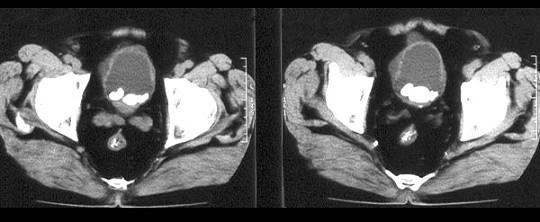

问题 男,58岁。大量无痛肉眼血尿伴血凝块1天,排尿困难1天。检查:血压120/75mmHg,脉搏82次/分,耻骨上及脐下压痛,叩诊浊音。 病人以肾癌收入院,肿瘤直径5.7cm。以下哪种手术方式最为合适 ( )

选项 A、右肾动脉栓塞 B、右肾切除 C、右肾、肾筋膜、肾周脂肪、肾蒂淋巴结切除 D、肿块局部切除 E、右肾输尿管及包括输尿管口的部分膀胱切除

答案 C